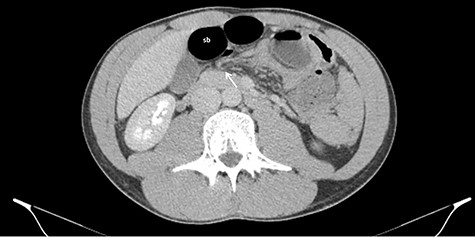

The abdomen had a tympanic percussion in the upper quadrants and tenderness in the epigastric area. He also presented with tachycardia, without other relevant findings. The laboratory studies revealed increased white blood cell count (WBC) and air-fluid levels on the abdominal x-ray (Fig. 1). Due to high suspicion of small bowel obstruction, an abdominal computed tomography was performed, revealing signs of an internal hernia of unknown type (Fig. 2).

Axial CT images of dilated small bowel (sb) with the respective mesentery converging to the hernia defect (white arrow) in the gastrohepatic ligament.